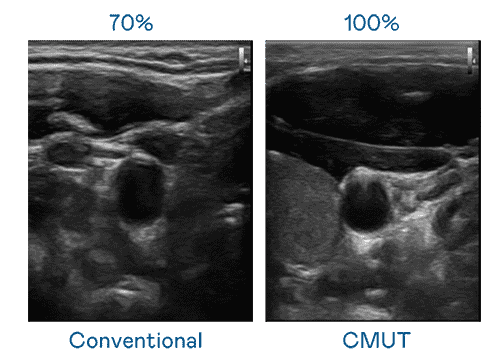

CMUT 技术是一种用电容式微机电元件来产生超音波讯号的技术。。。与传统 PZT 压电式技术相比,,,,CMUT 频宽增加 30%,,,更宽频的超音波讯号让影像解析度大幅提升,,,,是实现高影像品质医疗超音波扫描、、促进精准医疗发展的关键技术。。

超音波影像的解析度高低,,,,首先取决于探头能发出的讯号频宽。。Wepay CMUT 可提供高清晰的超音波讯号,,,提供高频宽、、、、高灵敏度、、、、影像纹理细节更高的超音波影像,,,协助医护人员缩短影像判读时间及利用精准的医疗影像进行诊断。。